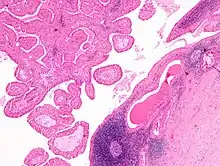

Low magnification micrograph of a Warthin tumor arising from the parotid gland.

Intermediate magnification micrograph of a Warthin tumor.

The appearance of this tumor under the microscope is unique. There are cystic spaces surrounded by two uniform rows of epithelial cells with centrally placed pyknotic nuclei. The cystic spaces have epithelium referred to as papillary infoldings that protrude into them. Additionally, the epithelium has lymphoid stroma with germinal center formation.